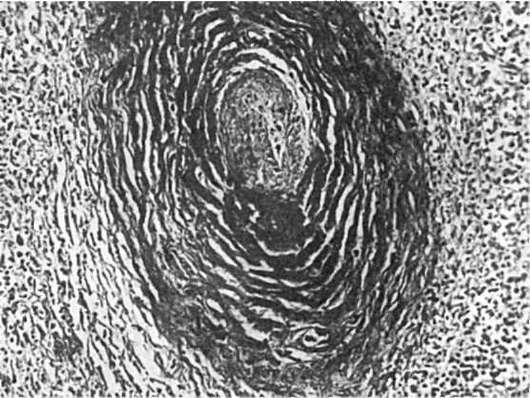

Третью группу составляют изменения склеротического характера. Они развиваются в исходе изменений первой и второй групп. Склероз нередко сочетается со свежими проявлениями дезорганизации соединительной ткани и васкулитами, что свидетельствует об обострении заболевания. К характерным признакам СКВ относится периартериальный

«луковичный» склероз в селезенке (рис. 177).

Рис.

177. Периартериальный «луковичный» склероз в селезенке при системной красной волчанке

ваются очаговые скопления лимфоцитов и плазматических клеток, продуцирующих иммуноглобулины. Встречается гиперплазия вилочковой железы с лимфоидными фолликулами. Отмечается повышенная фагоцитарная активность макрофагов. В селезенке и лимфатических узлах появляются белковые преципитаты, возникающие в результате диспротеиноза.